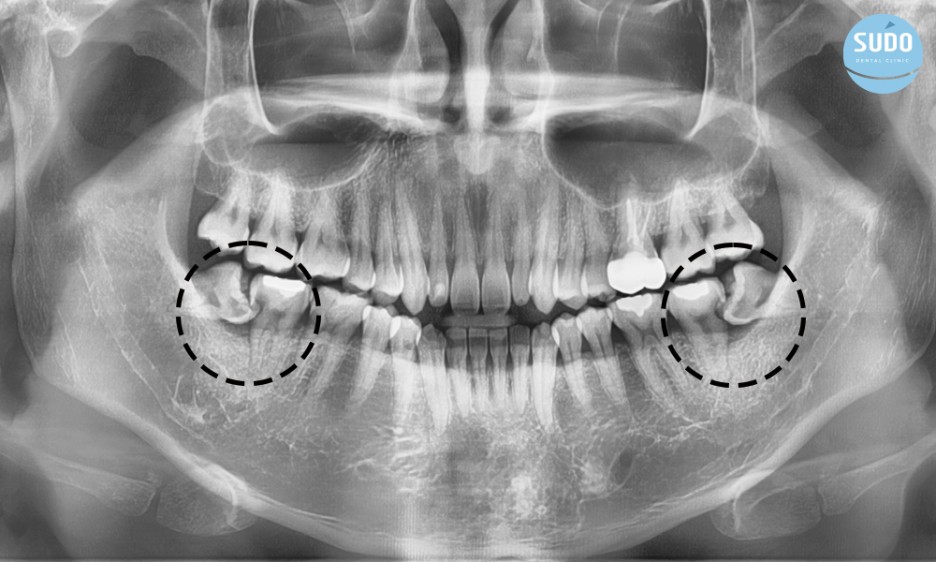

위 환자분은 파노라마 X-ray를 확인한 결과, 비스듬하게 누워있는 ‘부분 매복 사랑니’에 충치가 관찰되었습니다.

앞어금니에까지 신경을 침범한 ‘치아 사이 충치’ 또한 보이는데요, 매복 사랑니와 어금니 사이에 계속해서 이물질이 끼여 이가 썩은 것으로 사랑니 충치와 사랑 니로 인한 어금니 충치를 치료하기로 계획하였습니다.